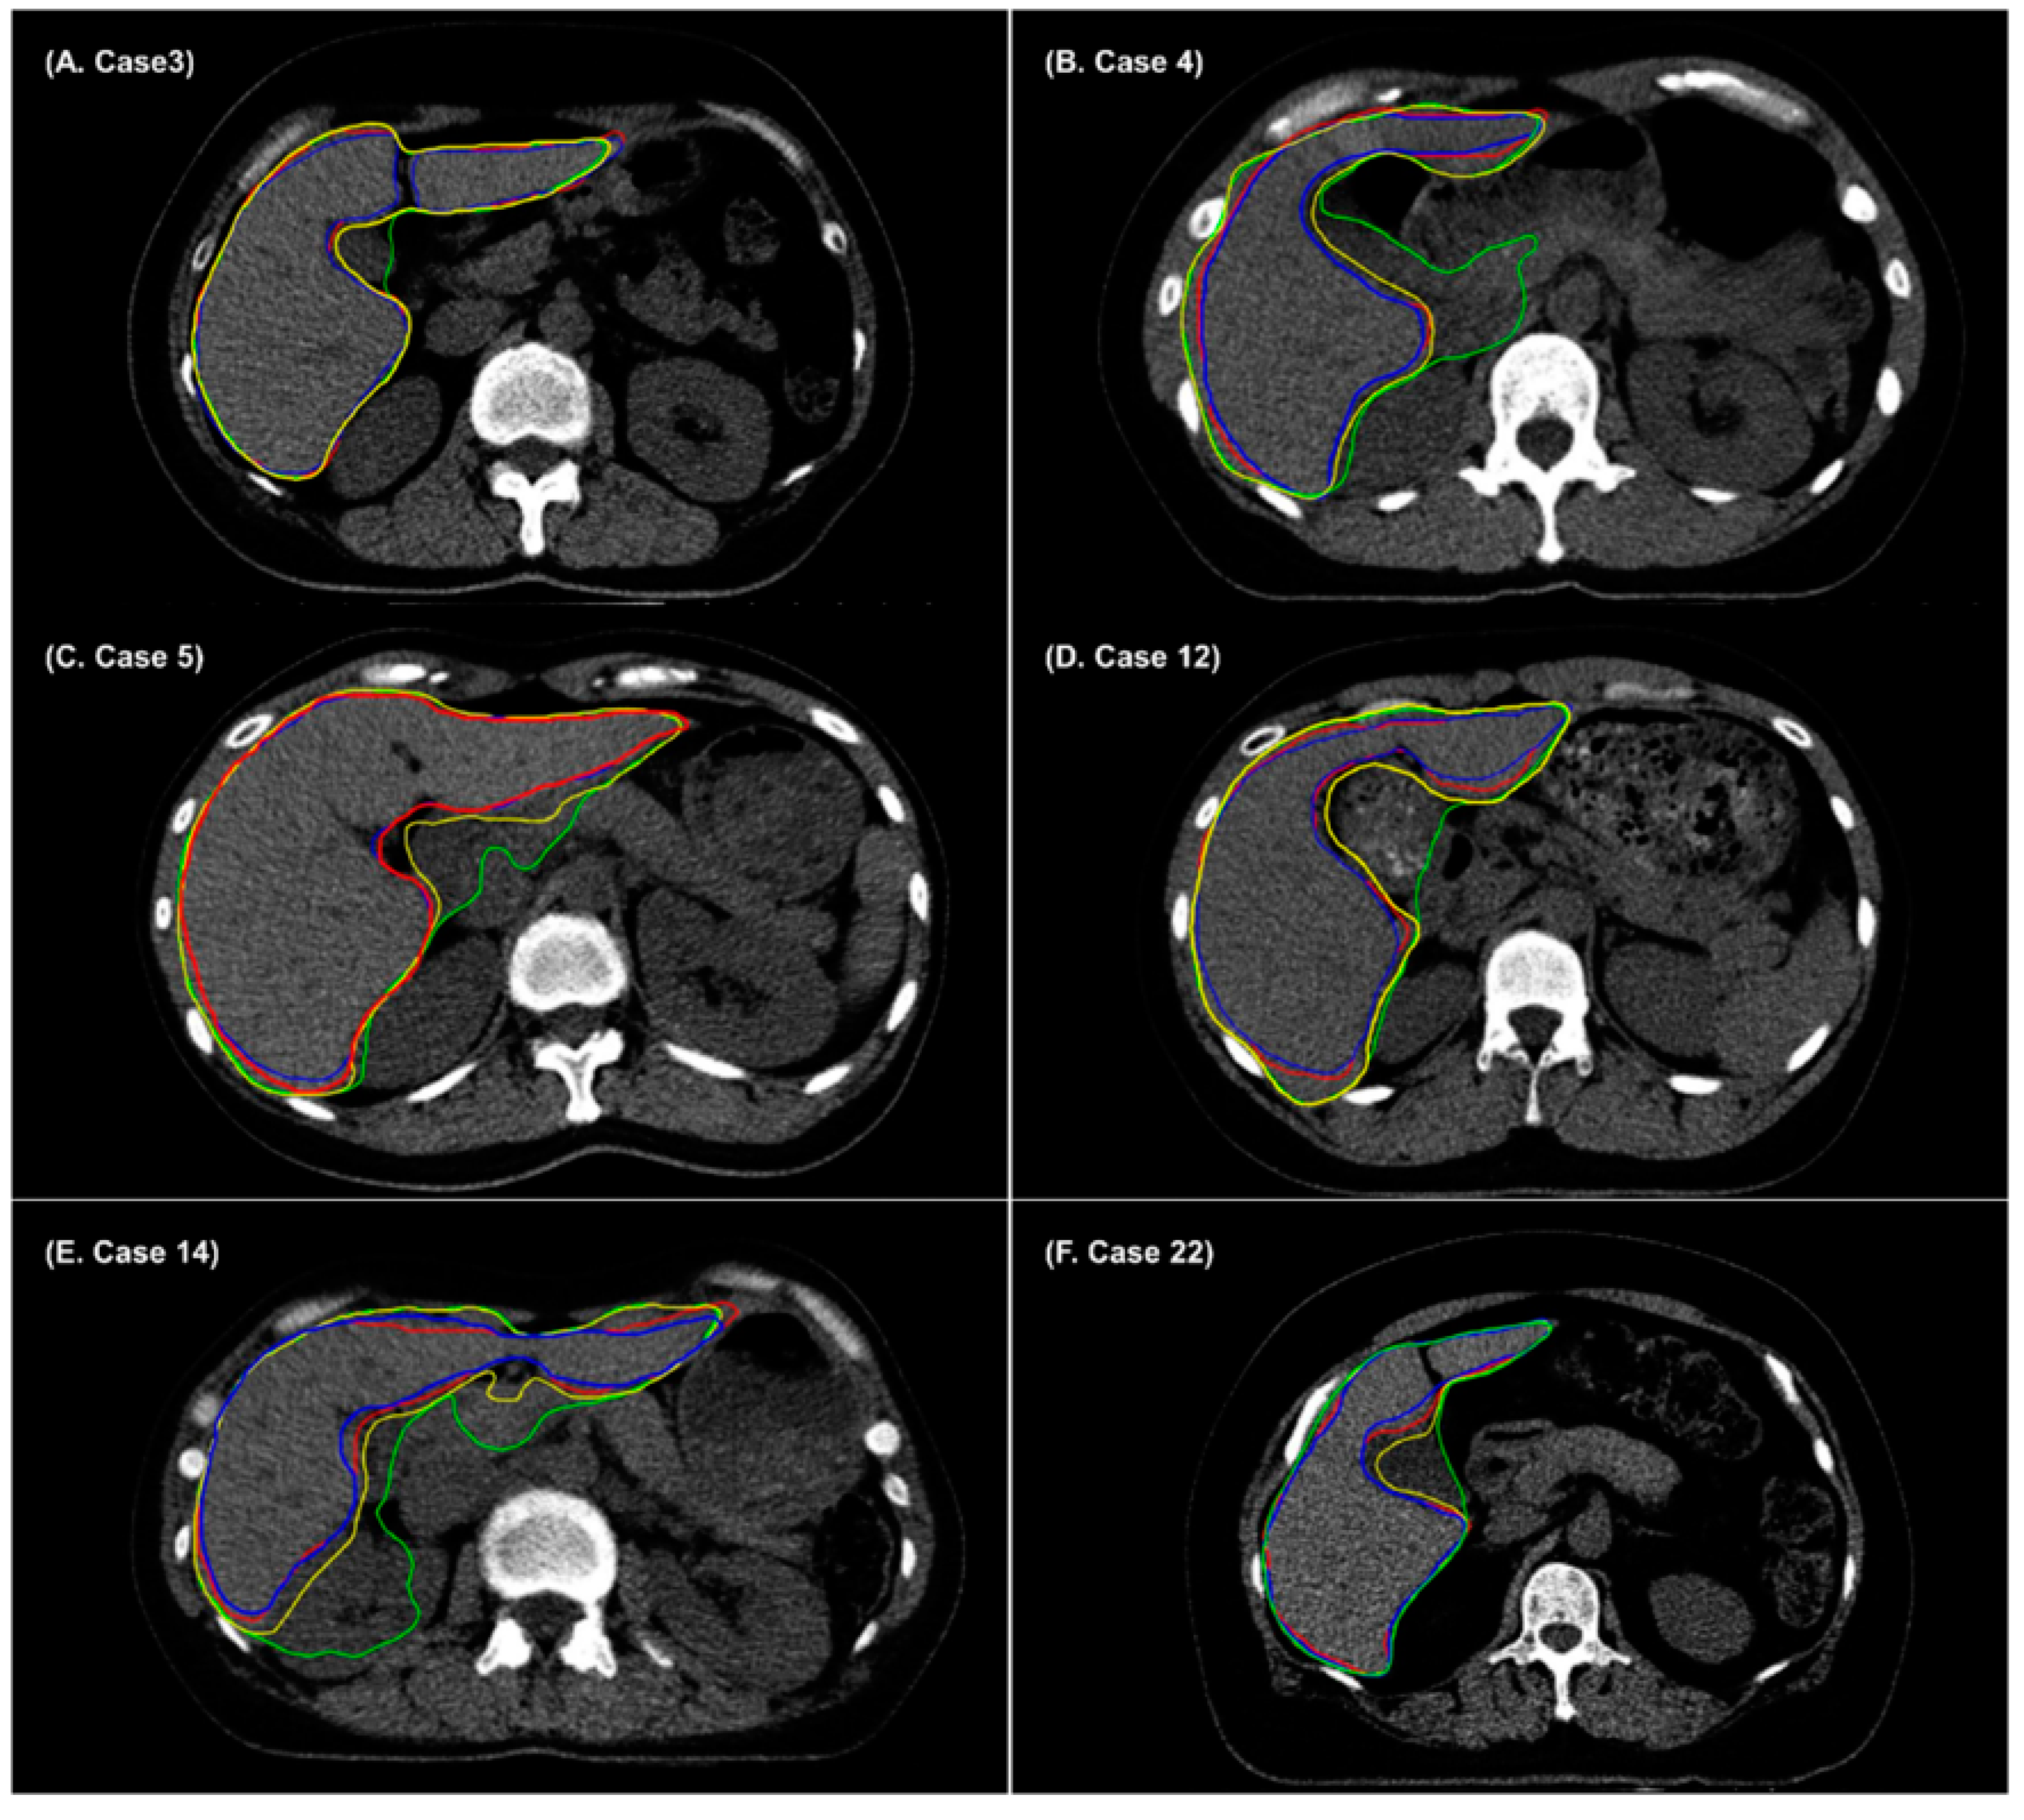

3. Results

4. Discussion